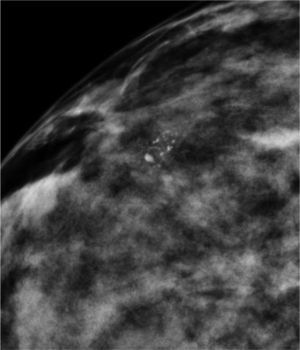

Las calcificaciones indeterminadas, como las demás, pueden ocupar una zona extensa de la mama (fig. 8), ser segmentarias (cuando ocupan un segmento) o estar agrupadas (fig. 9)6.

Gershon-Cohen y colaboradores describieron este tipo de calcificaciones como calcificaciones agrupadas, de tamaño entre 0,1 y 0,3mm, de forma irregular, pleomórficas y en ramificación lineal fina3.

Carcinoma ductal in situ (fig. 10). Es el carcinoma que con mayor porcentaje se presenta en forma de microcalcificaciones. Representa el 15-20% de los cánceres de mama3. Se detecta por mamografía más que por exploración clínica. Las microcalcificaciones corresponden a la necrosis central de la neoplasia, ocupan el conducto y son producidas por procesos proliferantes en los conductos terminales7. Suelen ser amorfas, espiculadas y con ramificaciones irregulares.